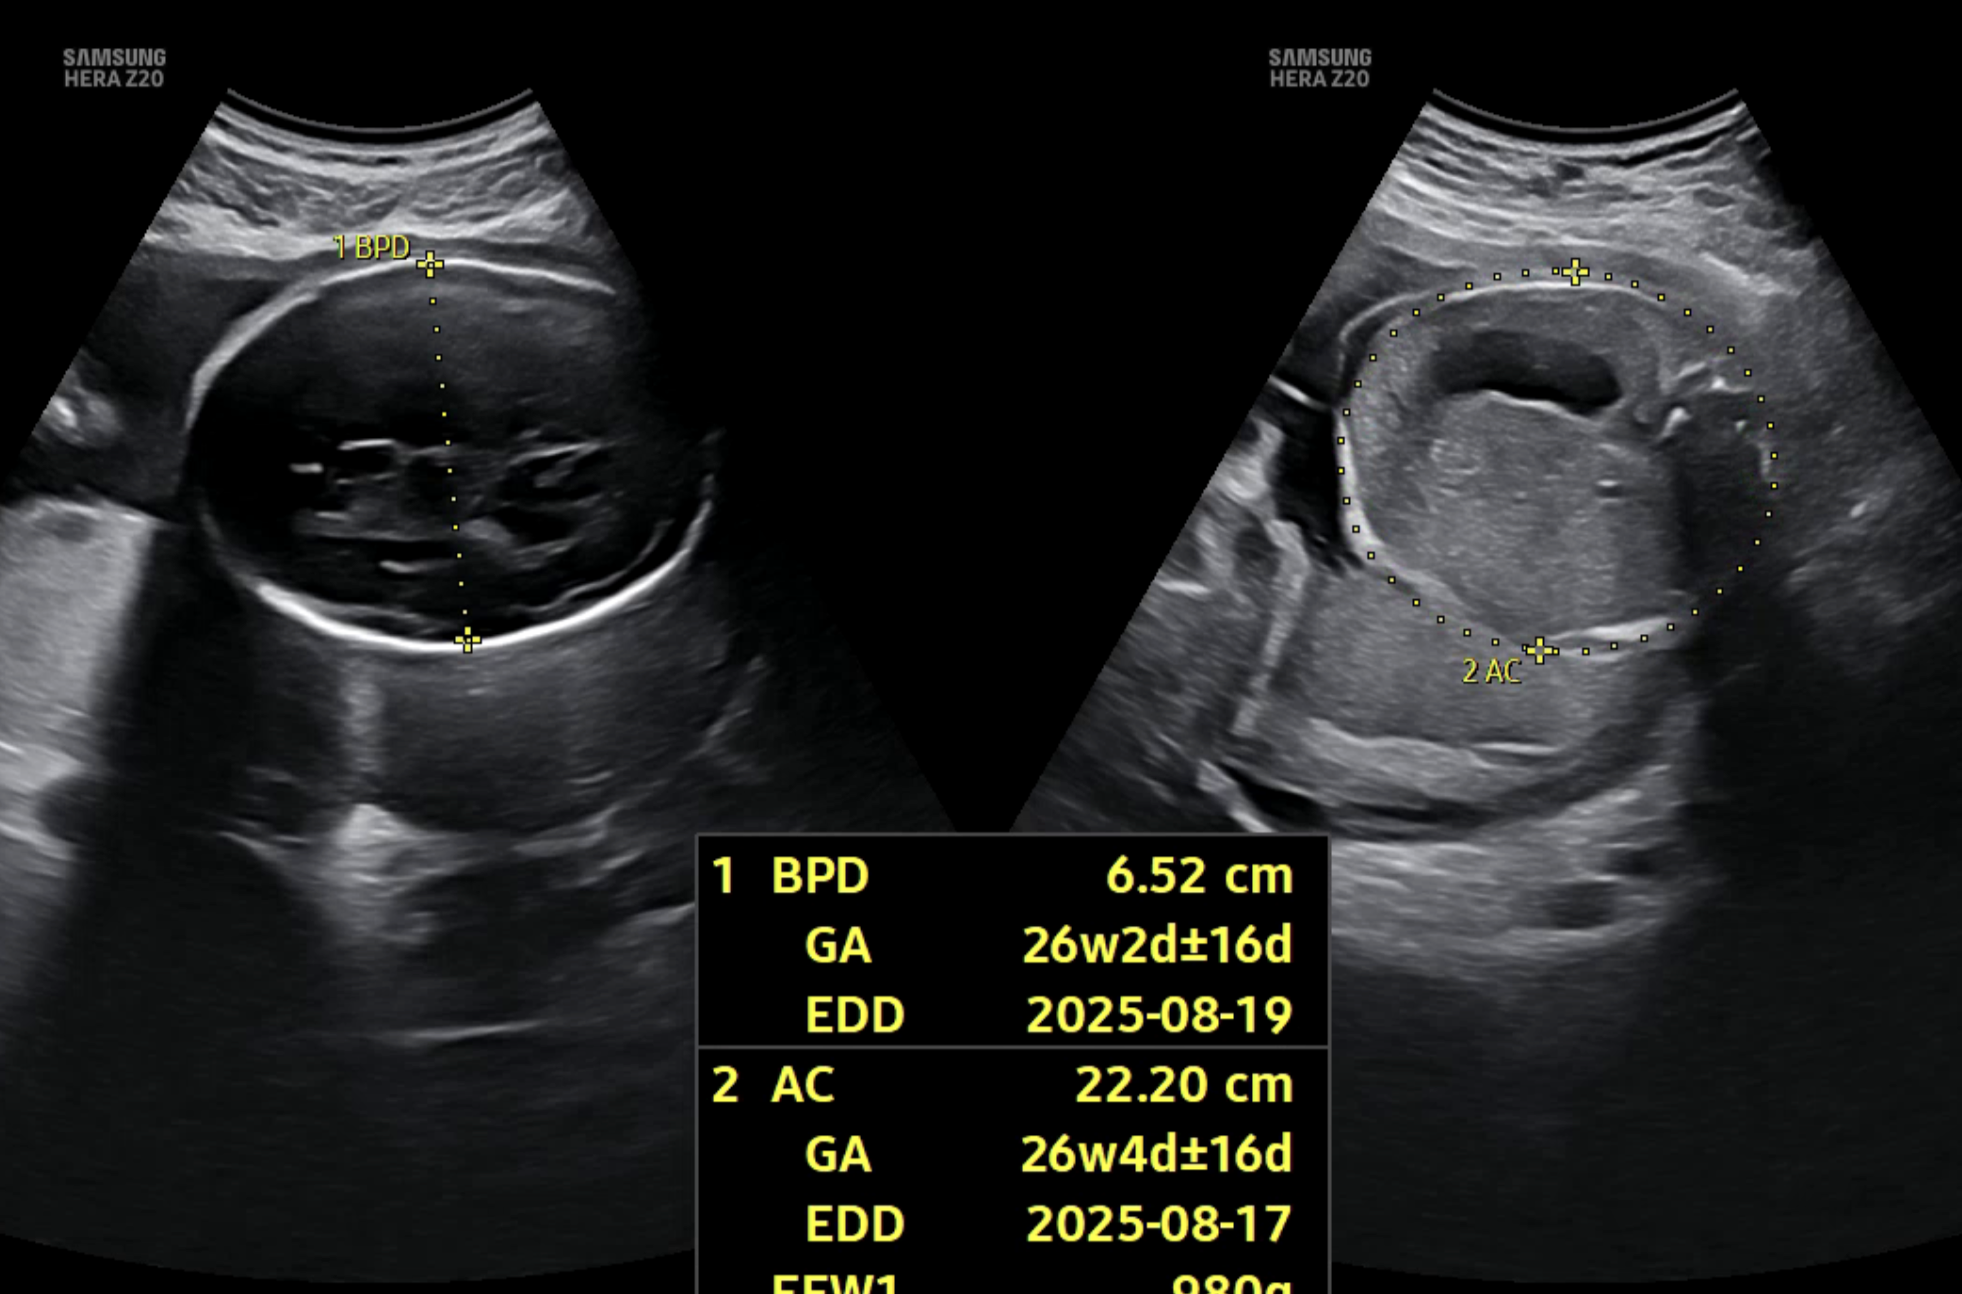

모델이 더 안정적으로 학습하려면 초반부터 모든 데이터를 학습에 사용하고, 확신이 없는 데이터까지 포함하도록 변경했다. 하지만 무엇보다도, 초음파 이미지라는 특성상 한 장의 이미지에 여러 부위가 함께 측정되는 경우도 많다는 사실을 간과하고 있었다. 실제 의료진도 하나의 이미지에서 AC, FL 등 여러 부위를 동시에 측정한다. 하지만 softmax 기반의 멀티 클래스 분류 방식은 무조건 하나의 클래스만 선택해야 하기 때문에, 이런 현실적인 상황을 반영하지 못했다. 결과적으로, 데이터 자체는 멀티 클래스 특성을 가지고 있는데, 모델은 억지로 싱글 클래스로 억지로 해석하고 있었다.

아래는 멀티 클래스 기반으로 변경한 뒤의 실제 예측 결과 예시이다. 단일 클래스 방식에서는 하나의 부위만 예측되던 이미지에서, 이제는 여러 부위가 동시에 높은 확률로 예측되는 모습을 확인할 수 있다.